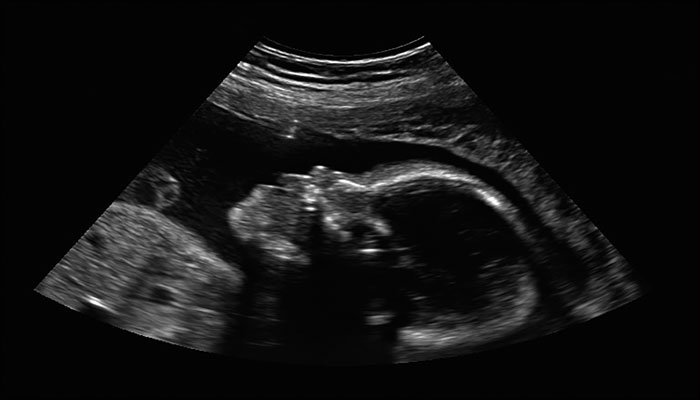

Theo các bác sĩ thực hiện ca mổ, ban đầu thông qua kết quả chụp cắt lớp, họ cho rằng vật thể dài 23,8 cm nằm trong bụng bệnh nhân là khối u và phải cắt bỏ.

Nhưng khi thực hiện ca phẫu thuật, các bác sỹ rất kinh ngạc khi biết khối u này thực chất là bào thai nặng 1,6 kg đã phát triển gần như hoàn chỉnh với tóc, bộ phận sinh dục, nhưng tứ chi bị biến dạng và không có miệng.

Các bác sĩ sau đó kết luận đây là hiện tượng là thai trong thai cực kỳ hiếm gặp với tỷ lệ 1/5 triệu ca sinh. Cho đến nay, thế giới cũng chỉ mới ghi nhận 200 trường hợp thai sinh đôi sống ký sinh trên cơ thể người sống như cậu bé này.